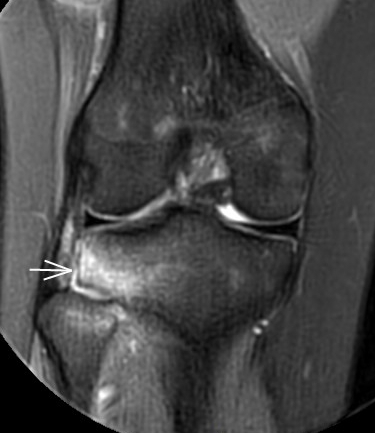

2. 運(yùn)動(dòng)后“打軟腿”——韌帶的“斷弦危機(jī)”

場(chǎng)景:打球急停后膝蓋不穩(wěn),走路像“踩棉花”

MRI偵查:揪出前交叉韌帶斷裂(呈“波浪狀”或連續(xù)性中斷)、內(nèi)側(cè)副韌帶損傷,防止關(guān)節(jié)“脫軌”

(內(nèi)側(cè)副韌帶損傷)